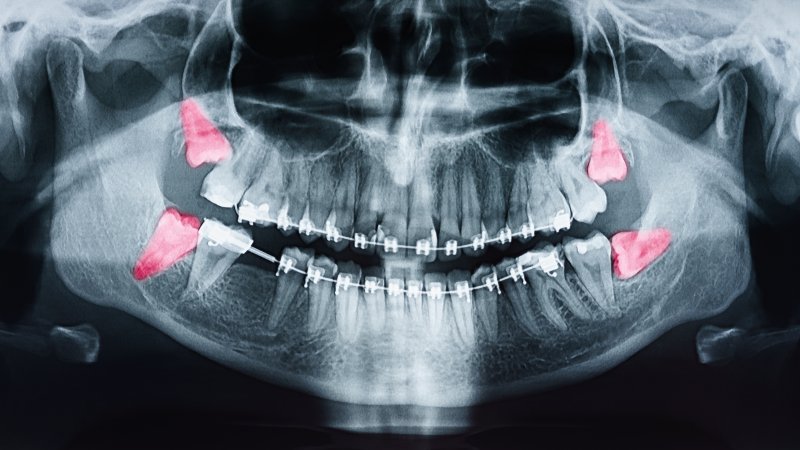

As you get older, your body undergoes many changes, and your oral health is no exception. From weaker bone structure to a more vulnerable immune system, aging can create trouble for your mouth. Because of this, gum disease, or periodontal disease, often becomes one of the most common concerns among older adults. But what causes it, and how can you head it off at the pass? Continue reading to learn more about periodontal disease and what you can do to fight back.